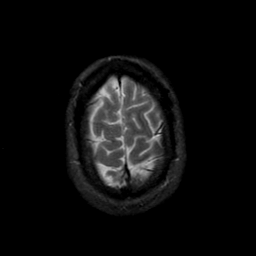

MR Study #23, January 26, 1992 -- Slice #44

[Home][Help][Clinical][Tour 1][Tour 2] Slice 44